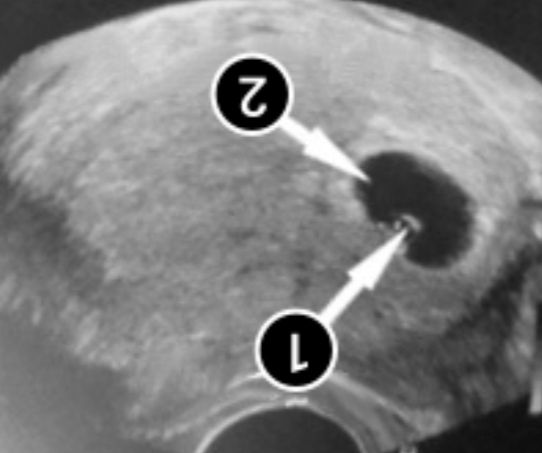

У нас получилось! Я беременна!

Сразу говорю одно изображение перевёрнуто ,мне не главное ,что бы вы сказали это разное фото и ТД ,это для сравнения)))

Азиза Себединова, а врач вам что сказала? На похожем узи была белая полоска. Мне не стали утверждать что это эмбрион, через 6 дней переделала уже был эмбрион и сб.

Светлана , Все уже узист сказала это эмбриончик маленький, успокоили отлегло ,на сб иду через недельку ❤️

Азиза Себединова, это одно и то же фото, и да, плодное яйцо определенно не пустое